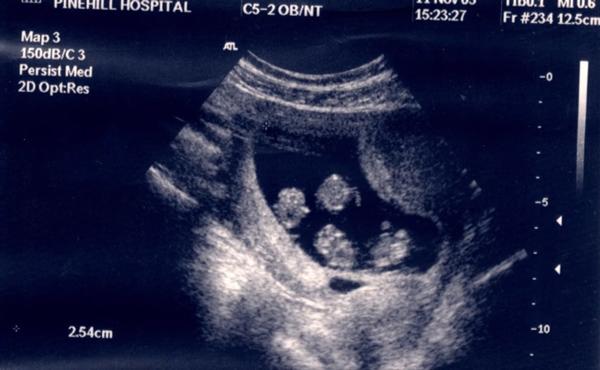

Và điều ngạc nhiên hơn nữa đã được tiết lộ trong buổi khám thai đầu tiên. Khi bác sĩ nói Julie đang mang đa thai, hai vợ chồng mỉm cười và nghĩ về một cặp song sinh. Nhưng không ai ngờ thực tế có đến 4 đứa trẻ đang cùng lớn lên trong bụng Julie.

Julie mang thai 4 cùng trứng cực hiếm trên thế giới.

4 bé Jessica, Holly, Georgie và Ellie giống hệt nhau về mặt di truyền. Trường hợp sinh 4 cùng trứng như Julie cực hiếm với chỉ lệ chỉ 1/64 triệu ca sinh. Bởi cả 4 rất giống nhau nên trong suốt 1 năm đầu đời, Julie chỉ có thể phân biệt các con bằng chữ cái viết tắt trên chân chúng.